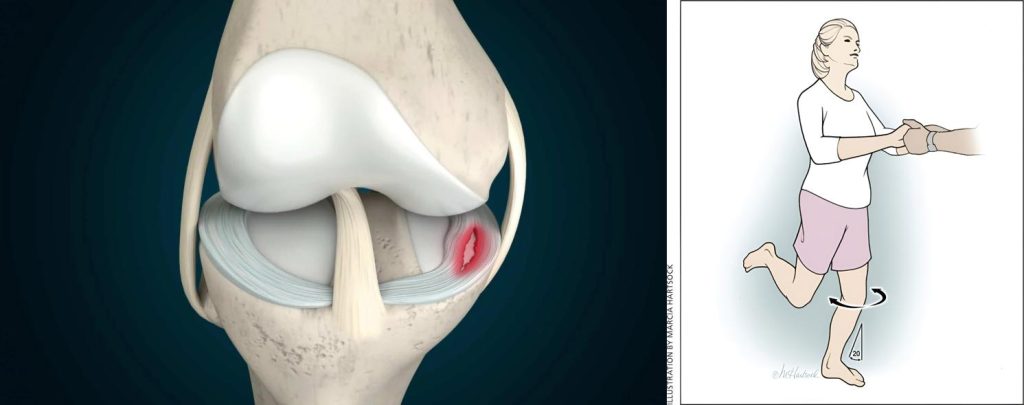

تست پارگی مینیسک زانو به همراه درمان

تست پارگی مینیسک زانو مجموعهای از روشهایی هستند که پزشک با کمک آنها بررسی میکند آیا مشکل زانو واقعاً از مینیسک است یا رباط و مفصل زانو دچار آسیب شده است. در این تستها زانو به شکلهای خاصی خم، صاف یا چرخانده میشود تا درد، صدا یا گیرکردن مفصل مشخص شود. نتیجه این تستها به […]